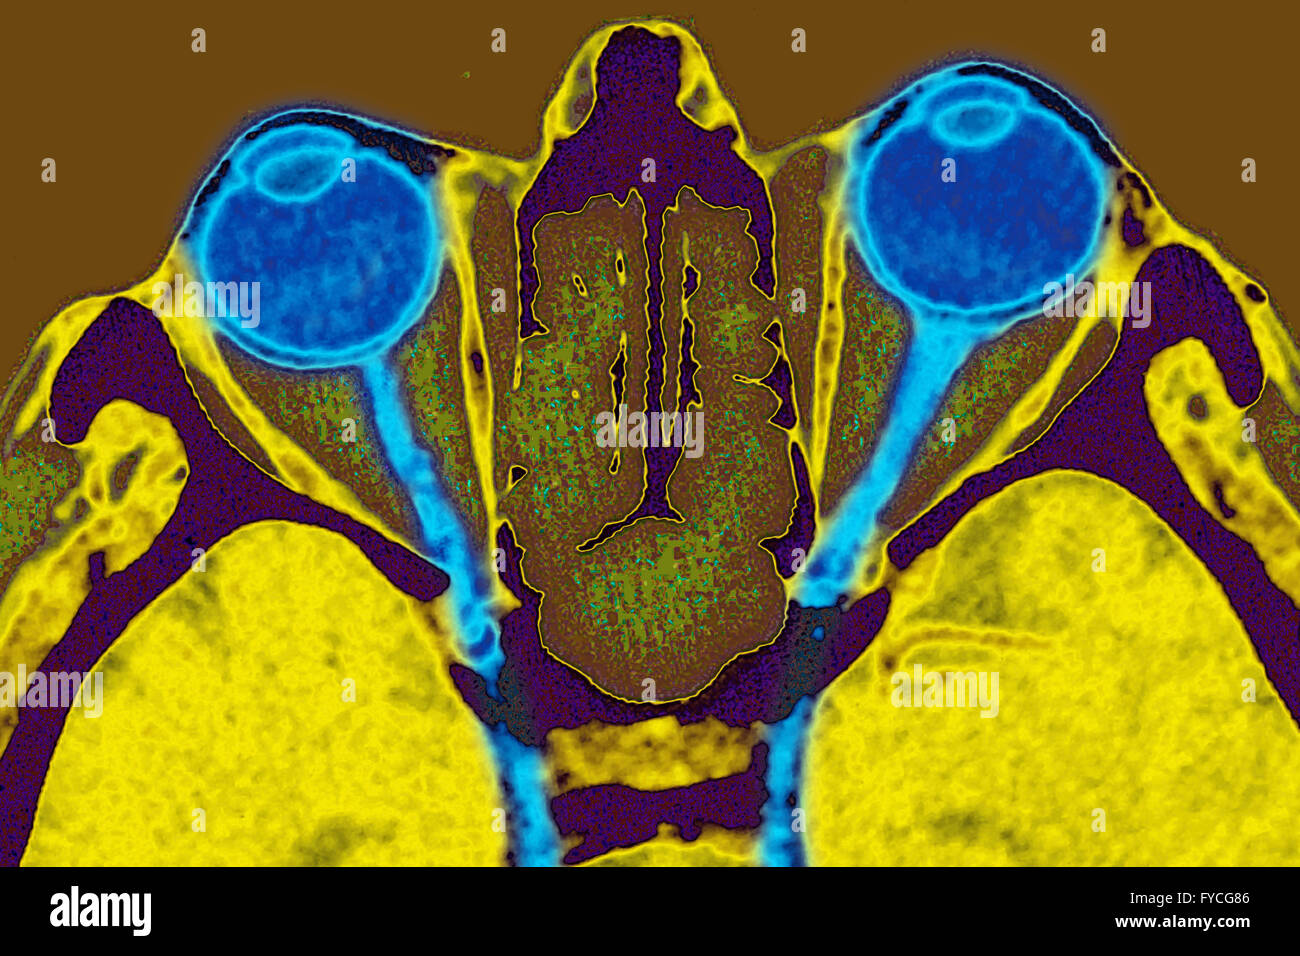

Il nervo ottico è il secondo di 12 paia di nervi cranici, ma è considerato come parte del sistema nervoso centrale; infatti, le fibre sono ricoperte dalla mielina prodotta dagli oligodendrociti, e il nervo ottico è avvolto nelle meningi (dura madre, aracnoide, pia madre). Tecnicamente, assieme al nervo olfattivo, non sono nervi ma una continuazione del sistema nervoso centrale.

Il nervo ottico - lungo circa cinque centimetri - lascia l'orbita attraverso il canale ottico, raggiungendo il chiasma ottico, in cui si assiste ad una parziale decussazione (incrocio) delle fibre nervose: infatti quelle provenienti dalle emiretine nasali si incrociano e proseguono nel tratto ottico controlaterale.

- parte intraorbitale: dal polo posteriore dell'occhio al foro ottico dello sfenoide

- parte intracanalicolare: attraverso il foro ottico dello sfenoide

- parte intracranica: dal foro ottico dello sfenoide giunge al chiasma ottico